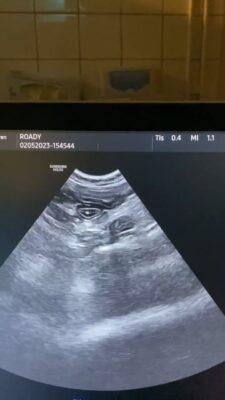

these are the photos of the bloodwork and from the ultrasound

This post is about a patient of mine that came to me on Wednesday.

General information and history: Cat, male, not castrated, 11 years old with different behaviour since 3 days. According with the owners, the cat didnt want to eat and drink for 3 days. Also he wasnt active and he was hiding. The owners didnt have…